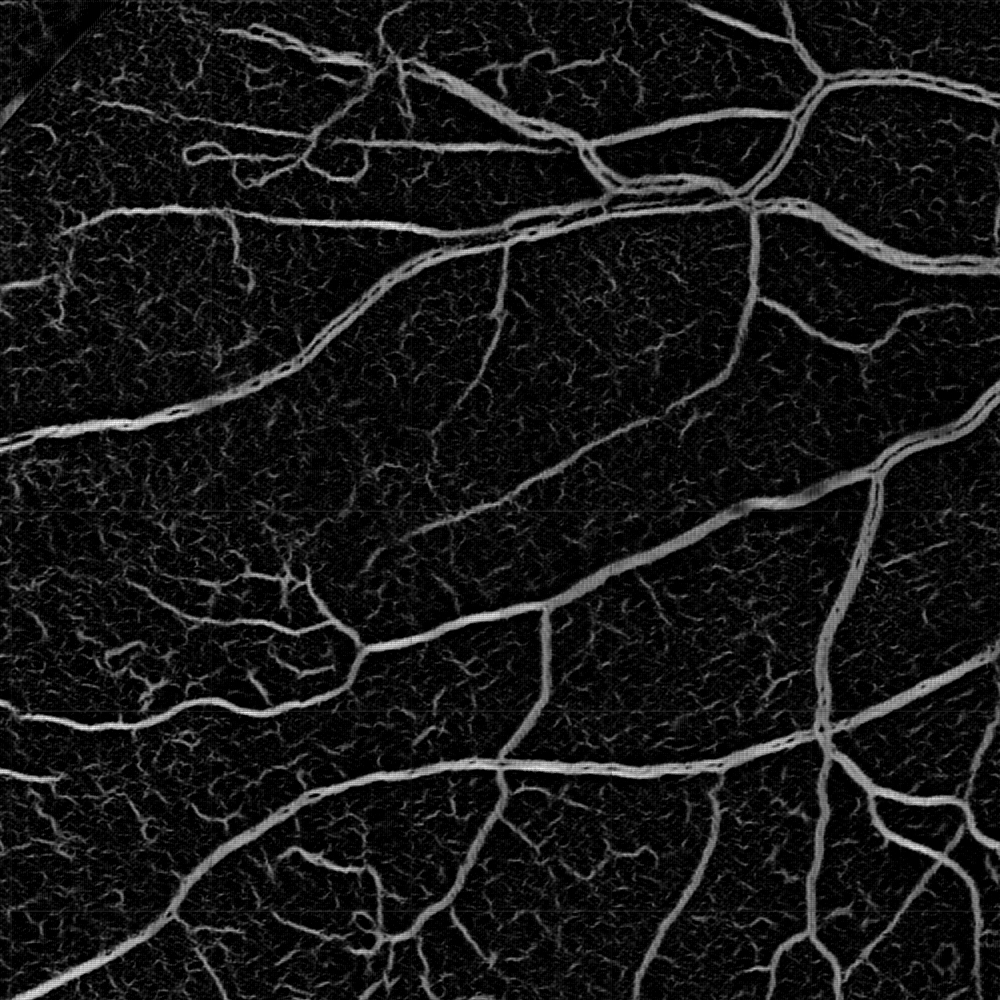

Medical images suffer from the distribution shift caused by the discrepancy in imaging acquisition protocols. Images can appear in different contrast, resolution and range of intensity values, even within the same modality. A set of examples is shown in Fig. 1. This obstacle severely impedes the learning-based algorithms reaching clinical adoption. Therefore, much effort has been spent on solving the domain generalization (DG) problem so that the deep models can robustly work on out-of-distribution (OOD) data. There are three major types of solutions: data augmentation [23, 18], meta-learning [6, 14] and domain alignment [24]. The first two strategies aim to improve the model’s generalizability by either augmenting the source domain with additional data or replicating the exposure to OOD data during training. In contrast, the domain alignment strives to align the distribution of the target domains in either image [8] or feature space [1, 15].

Fig. 4 shows a qualitative ablation study: it illustrates that the intensity representation may miss large vessels in the very high-resolution HRF images, while remains robust. In contrast, provides sharper delineation for very thin vessels in ROSE. The fusion of both pathways outperforms either pathway for most scenarios. These observations are further supported by the quantitative ablation study in Fig.6. We note that and can be used as synthetic angiograms that provide both enhanced vessel visualization and model interpretability.